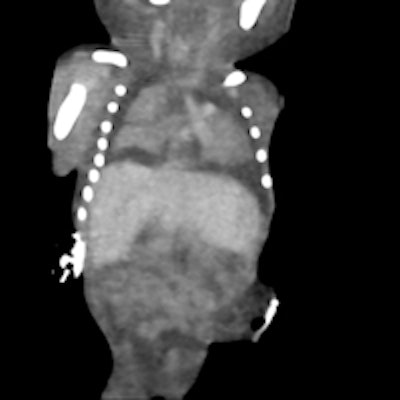

3D skeletal reconstruction shows a hemivertebra and extra rib.A conventional autopsy was performed on each fetus after CT scanning by an experienced pediatric/neonatal pathologist. The CT scans were analyzed by a perinatal radiologist (Constantine herself), together with a pediatric/neonatal pathologist (co-author Dr. Lynette Moore, an associate professor).